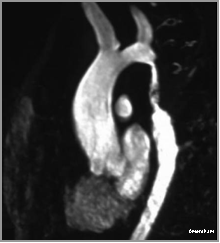

Contrast enhanced MRA shows long segment coarctation of the aorta